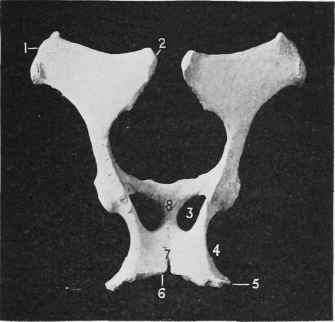

Fig. 294. - Pelvis (Superior Aspect).

1 Anteroinferior Spine of Ilium. 2 Supero-posterior Spine of Ilium.

3 Obturator Foramen. 4 Lateral Ischiatic Notch. 5 Tuberosity of Ischium. 6 Ischiatic Arch. 7 Symphysis Ischii. 8 Symphysis Pubis.